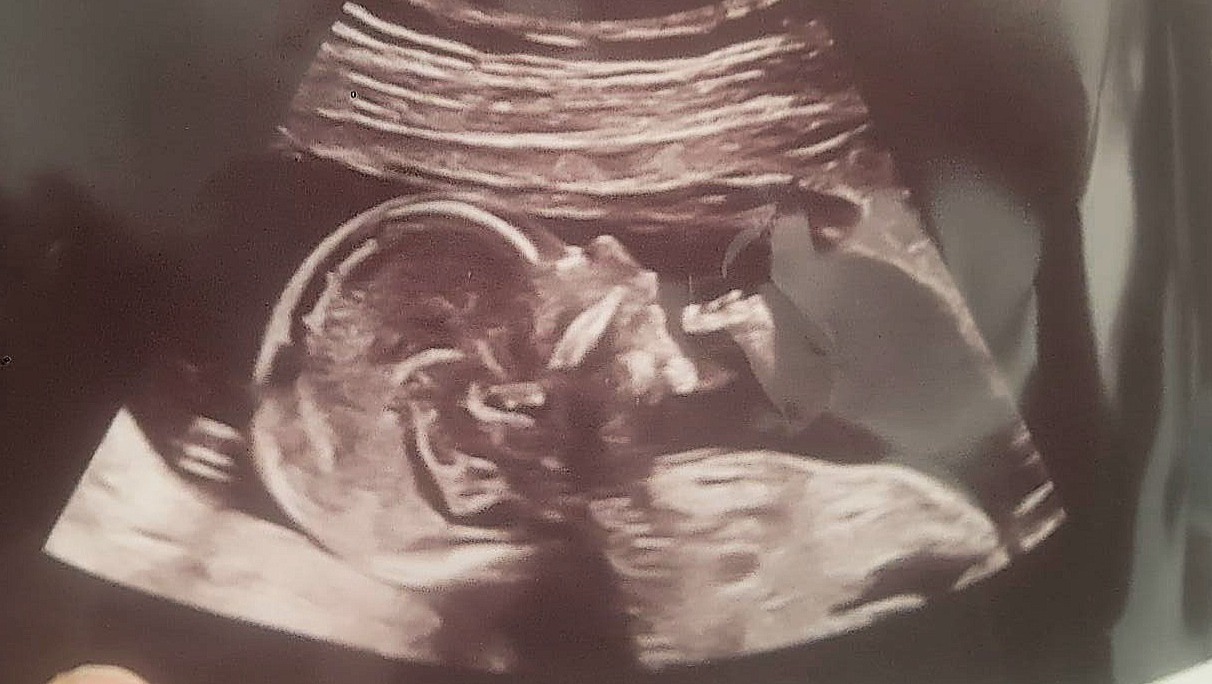

During a routine ultrasound, we received the devastating news that Thomas has a lower urinary tract obstruction, causing his bladder to back up into his kidneys and low levels of amniotic fluid. This condition has led to complications including a partial rupture of his bladder, kidney damage, and bilateral clubbed feet.